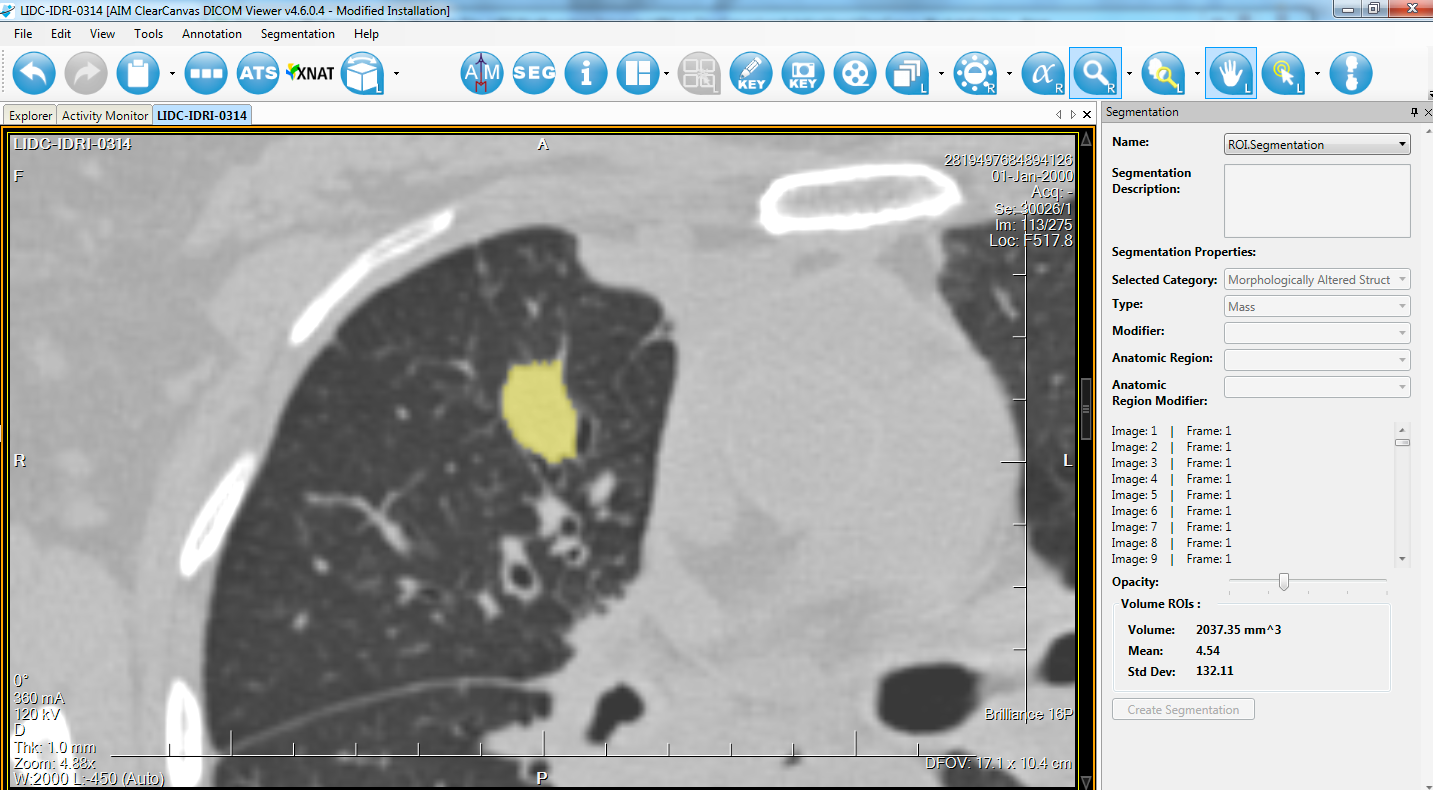

Лазерная камера для печати медицинских изображений на пленке стандарт dicom